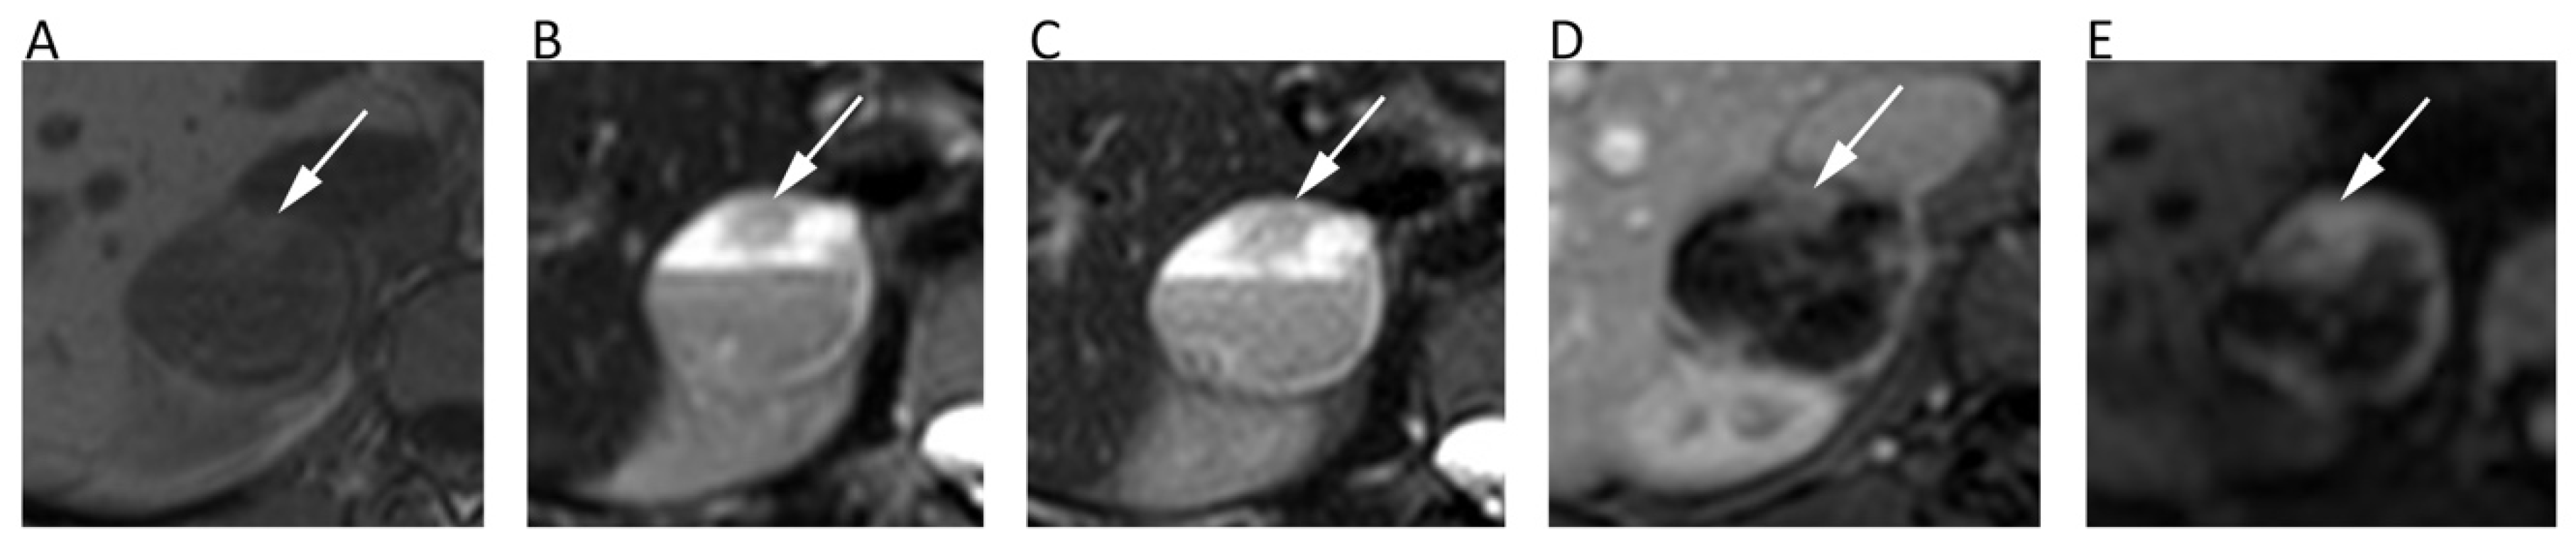

Regarding cervical cancer, a lesion that is visible with a conventional MRI indicates a stage IB or higher, with the tumor usually being well visible on T2-weighted. However, DWI has been shown to improve small cancers’ detection after biopsy, since post-procedure inflammatory changes may alter the normal anatomy [58]. DWI is also more accurate than T2-weighted at assessing tumor size and improves the accuracy in detecting parametrial invasion (tumors with parametrial invasion have significantly lower ADCs than those without (p = 0.034) [59] and peritoneal spread of disease (90% sensitivity, 95.5% specificity) (Figure 8) [58]. When cervical cancer is not eligible for surgery, ADC is a useful biomarker for predicting response to chemo-radiotherapy [57]. Studies have shown that a low pre-treatment ADC is a predictor of good response and an early ADC increase, even before the reduction of tumor size [57].

Figure 8.

A cervical cancer without parametrial invasion in a 70-year-old woman. The lesion (arrows) is slightly hyperintense compared to normal cervical stroma on sagittal (A) and axial (B) T2w, whereas it is highly hyperintense on b = 800 DWI (C) and hypointense on the corresponding ADC map (D), with moderate contrast enhancement on fat-suppressed 3D-GRE T1w (E).